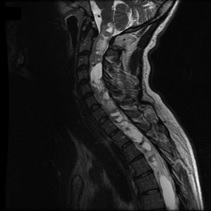

Upper Spine (Cervical)

Ependymoma

Spine Schwannoma, Spine Tumor, MRI

Ependymoma, Upper Spine, tumor, MRI

• Spinal Cord Tumors: Tumors that grow along the Spinal Cord[Plotkin, 2012] have a slower rate of growth than brain tumors.